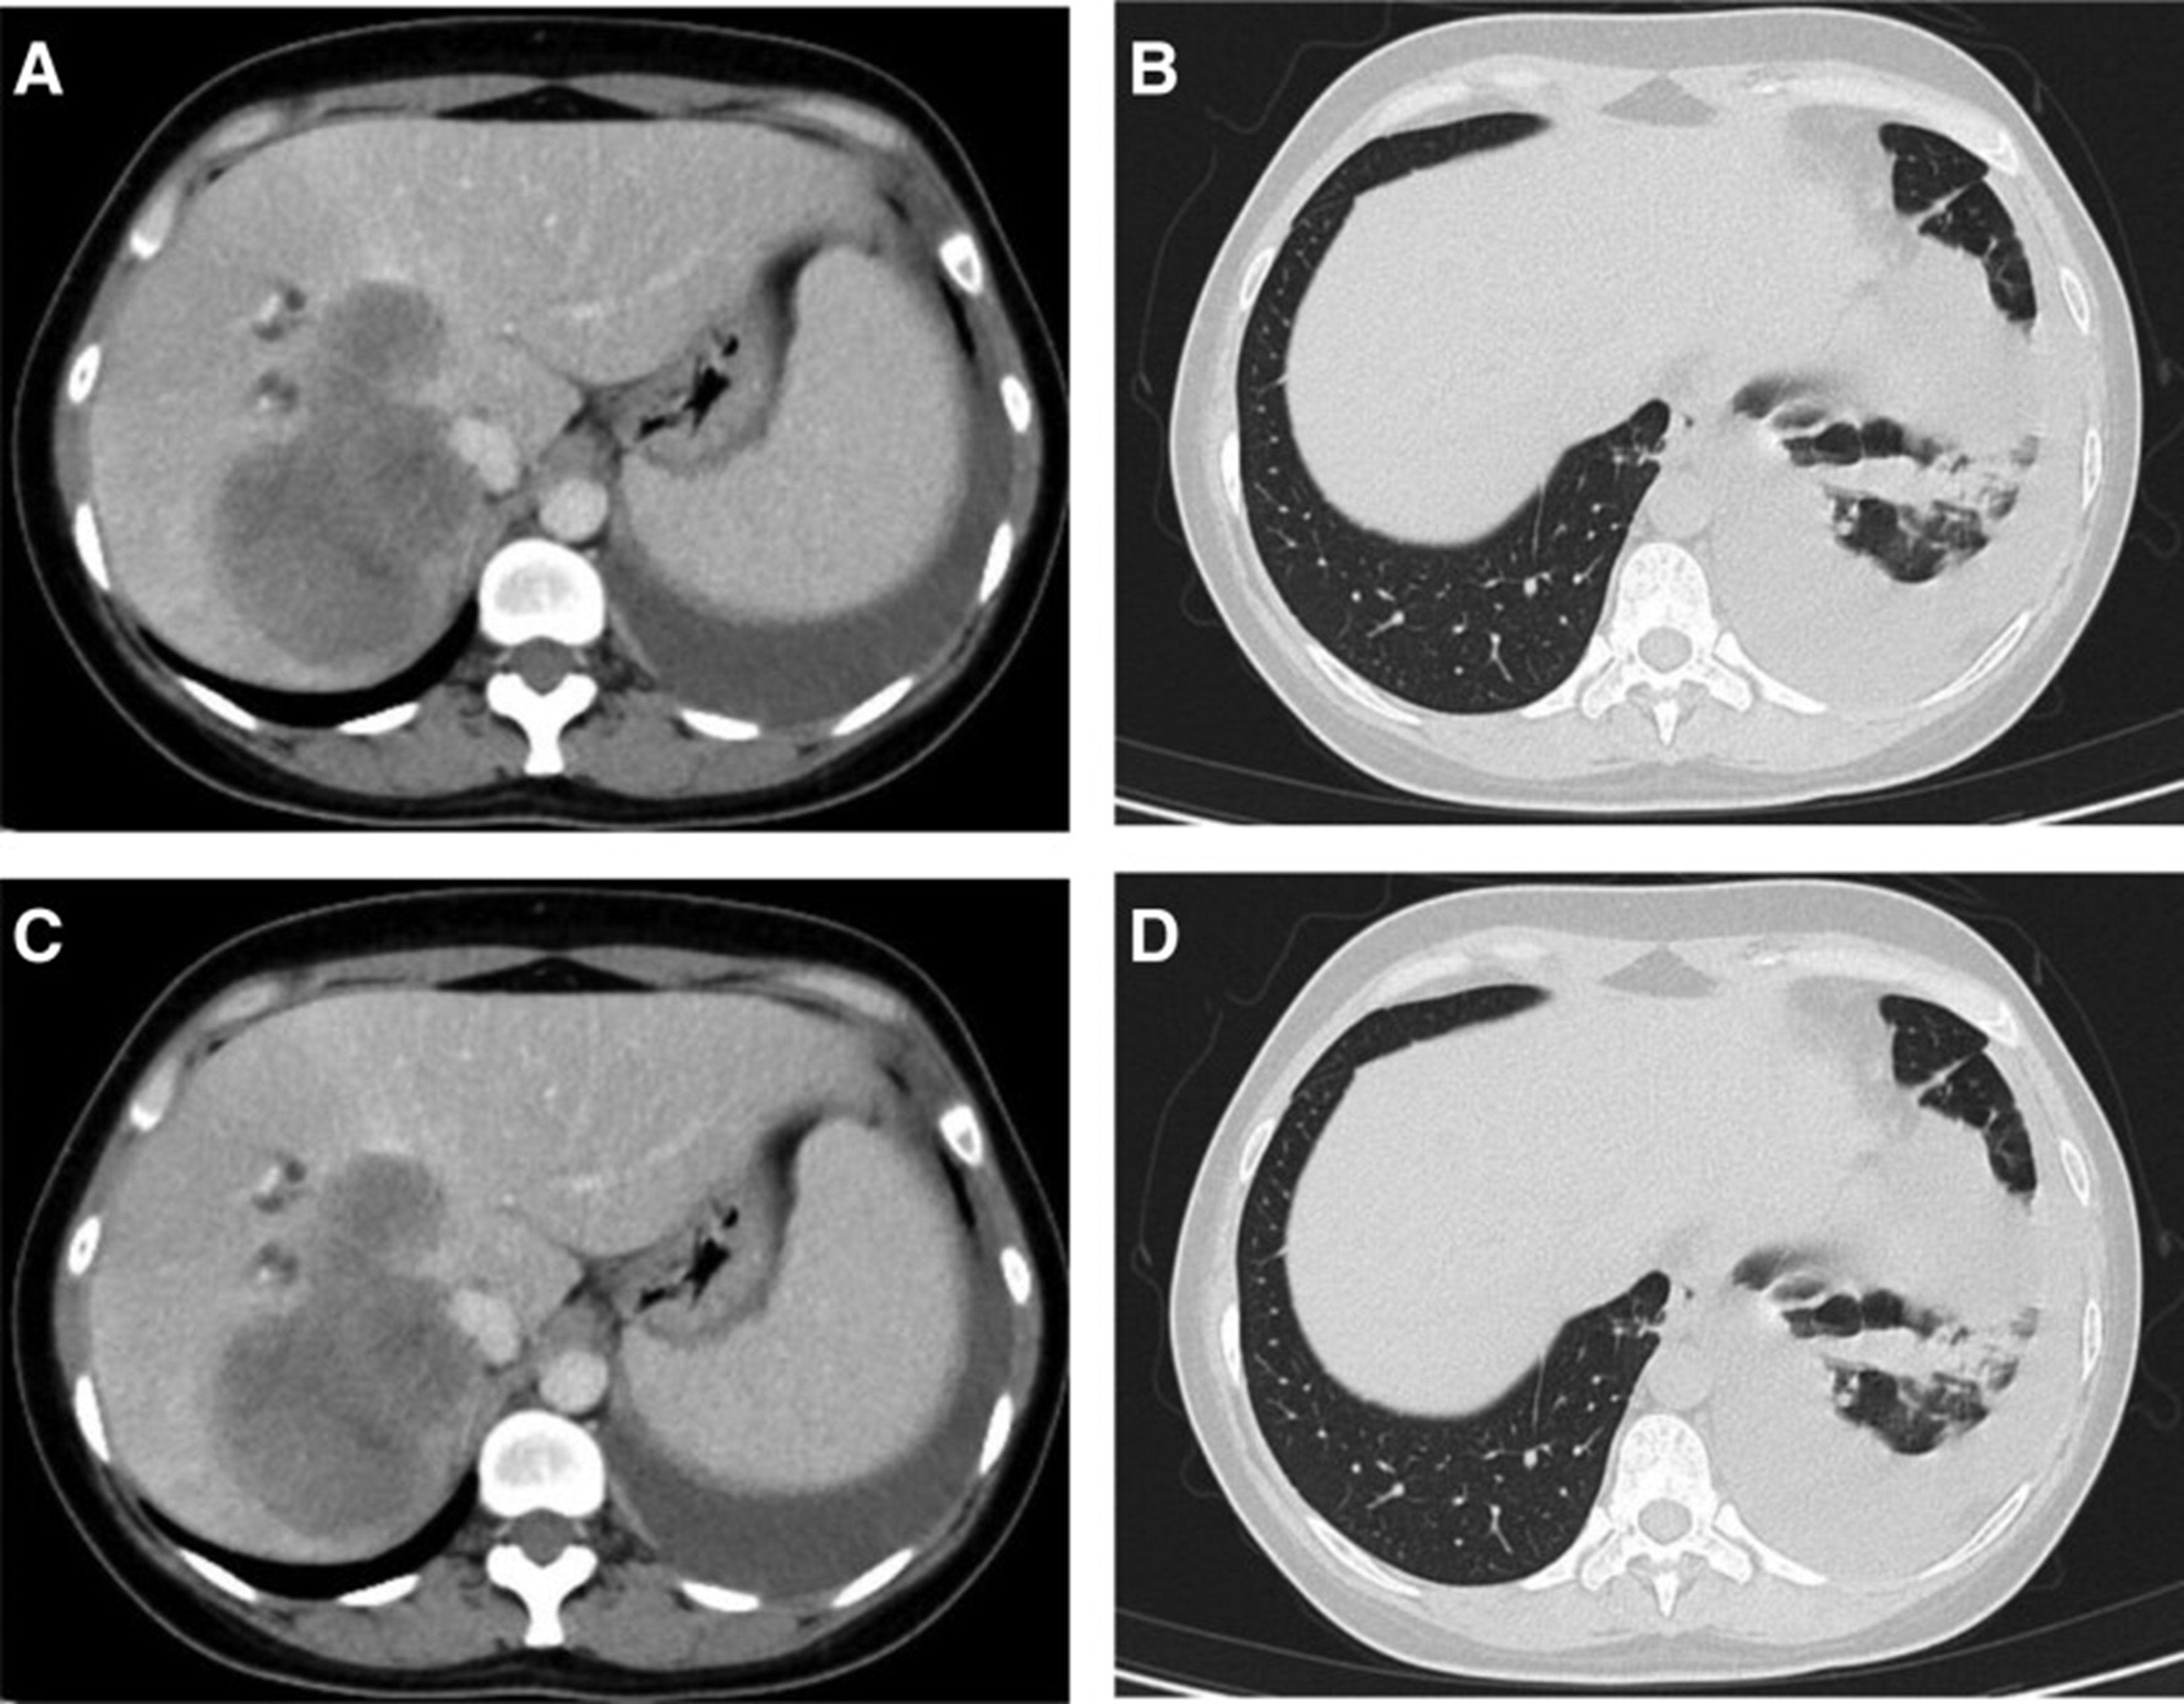

2020年5月1日,患者开始口服艾乐替尼靶向药物进行治疗,2020年6月25日复查,确定治疗效果为PR(部分有效)(根据RECIST1.1)显示肺病灶和肝转移灶明显减少(图1)。(图 3D-F)。2020 年 8 月 27 日复查确定治疗效果为疾病进展(PD, progressive disease),根据 RECIST1.1显示肝脏病变变大(图 1)(图 4A-D)。进行了第二次肝活检,随后的病理学显示“(肝)低分化癌,结合免疫组织化学分析考虑肺腺癌转移”。组织活检进行了第二轮基因检测,结果显示“BRAFV600E 14.79%,EML 4-ALK fusion 14.47%”(图 1)(图 5)。2020年9月20日,对患者我以为用恩沙替尼联合达拉非尼靶向治疗。治疗开始后,患者出现明显发热、寒战、乏力和厌食。期间患者左侧出现大量胸腔积液,胸腔积液中脱落细胞为“非典型细胞,考虑为腺癌”。随后,该患者接受了 1 次胸腔内铂输注。

和 2020 年 8 月.jpg)

图 5:2020 年 6 月(A 和 B)和 2020 年 8 月(C 和 D)的 CT 扫描。CT = 计算机断层扫描。